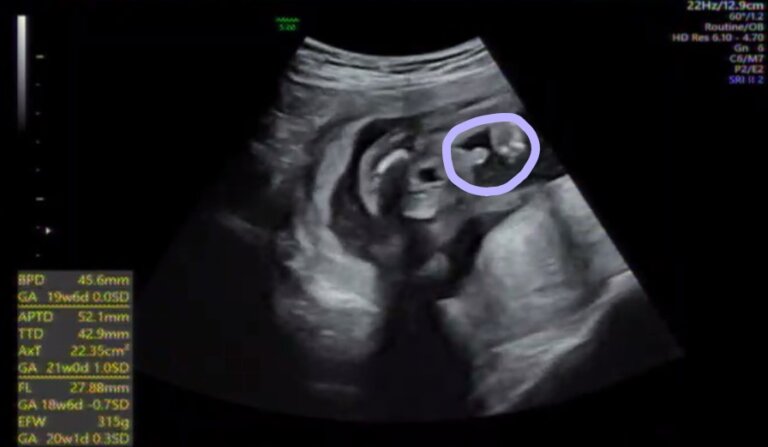

でっぱりんは「我が子動きすぎじゃない? 驚いたことを明かし、動いている赤ちゃんのエコー動画を掲載。 初マタ」「#12月出産予定妊娠週3日(w3d)の赤ちゃんのエコー写真です。投稿も募集しています。 125cm、353gでした。 胎盤に隠れて、また顔見せてくれませんでした(><) 性別は女の子でした。 周りにも女の子って言われてました。 エコー中元気に動きすぎて先生と笑った4dエコー画像 12週 手足、へその緒が見えてきました。まだ2頭身です。 14週 3頭身になってきました。 17週 全身が一画面にかわいく写る週数です。 18週 リアルモードだと本当にお腹の中をのぞいているよう! 21週

第1子妊娠 あいのり でっぱりん 赤ちゃんの最新エコー画像を公開 元気に動いてる事に感動 スポーツ報知